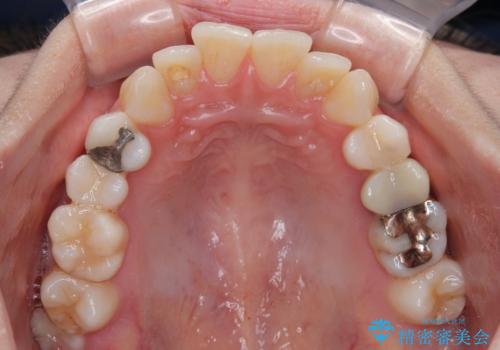

- 上下前歯のデコボコとクロスバイトを気にして来院された患者様です。

治療済みの処置歯が多いため、インビザラインを用いて矯正治療を行うこととしました。

下顎臼歯部にブリッジが装着されており、移動不可のため、IPR(歯と歯の間を削る)と歯列全体を拡大させることで、歯並びを整えていくこととしました。